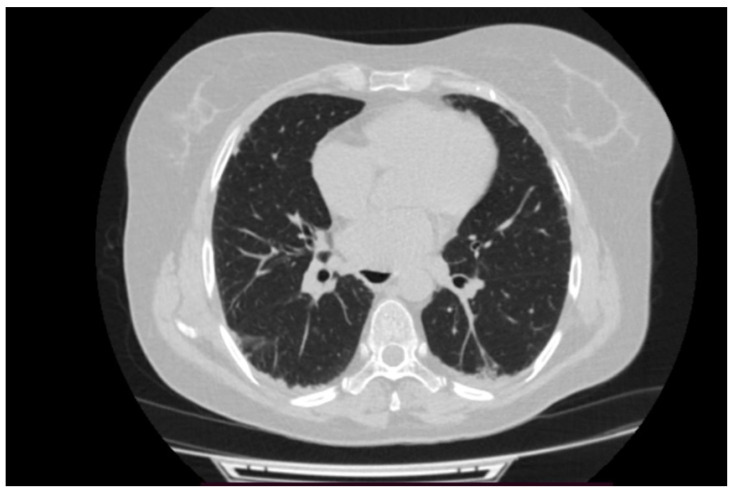

背景和临床意义:抗合成酶综合征(ASyS)是一种罕见的自身免疫性疾病,其特征是存在抗氨基酰基-t核糖核酸(RNA)合成酶自身抗体,通常与间质性肺疾病(ILD)、炎症性肌病和关节炎有关。其他临床特征可能包括雷诺现象和“机械师之手”。在抗合成酶抗体中,抗pl -12与显性或孤立性ILD明显相关,并且可能在没有临床明显肌炎的情况下发生,从而使及时诊断复杂化。病例介绍:我们报告一位45岁的非吸烟女性患者,既往诊断为血清阴性类风湿性关节炎(RA),出现进行性呼吸困难、干咳和恶心症状。高分辨率计算机断层扫描显示非特异性间质性肺炎(NSIP)模式。尽管肌酸激酶和乳酸脱氢酶水平正常,血清学检查显示抗pl -12和抗ro52抗体阳性,支持抗合成酶综合征的诊断,无肌炎,符合conors和Solomon的ASyS诊断标准。皮质类固醇和环磷酰胺治疗可诱导临床和呼吸功能改善,而硫唑嘌呤用于维持。结论:该病例强调了抗合成酶综合征的临床异质性,并强调了在没有肌炎的情况下,抗pl -12相关ILD所带来的诊断挑战。重要的是,该研究表明,在已有风湿病诊断的患者中,非典型肺部表现的出现需要重复血清学评估,以评估ASyS和其他自身免疫性疾病。早期诊断和免疫抑制治疗对优化预后至关重要。

Background and Clinical Significance: Antisynthetase syndrome (ASyS) is a rare autoimmune entity defined by the presence of anti-aminoacyl-t ribonucleic acid (RNA) synthetase autoantibodies and classically associated with a triad of interstitial lung disease (ILD), inflammatory myopathy, and arthritis. Additional clinical features may include Raynaud's phenomenon and "mechanic's hands". Among antisynthetase antibodies, anti-PL-12 is notably associated with predominant or isolated ILD and may occur in the absence of clinically evident myositis, thereby complicating timely diagnosis. Case Presentation: We are presenting a 45-year-old non-smoking female patient with a prior diagnosis of seronegative rheumatoid arthritis (RA) who developed progressive dyspnea, dry cough, and sicca symptoms. High-resolution computed tomography revealed a nonspecific interstitial pneumonia (NSIP) pattern. Despite normal creatine kinase and lactate dehydrogenase levels, serological work-up revealed positive anti-PL-12 and anti-Ro52 antibodies, supporting a diagnosis of antisynthetase syndrome without myositis, fulfilling the diagnostic criteria for ASyS per Connors and Solomon. Treatment with corticosteroids and cyclophosphamide induced clinical and functional respiratory improvement, while azathioprine was initiated for maintenance. Conclusions: This case underscores the clinical heterogeneity of antisynthetase syndrome and highlights the diagnostic challenge posed by anti-PL-12-associated ILD in the absence of myositis. Importantly, it demonstrates that in patients with pre-existing rheumatologic diagnoses, the emergence of atypical pulmonary manifestations warrants repeat serologic evaluation to assess ASyS and other autoimmune conditions. Early diagnosis and immunosuppressive treatment are essential to optimize outcomes.